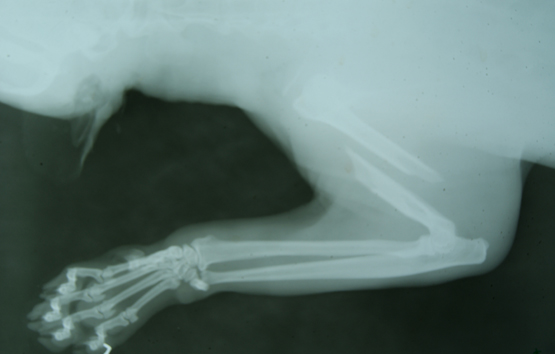

“Debido a esta situación de desnutrición, el animal sufrió una fractura cerrada en el tercio medio del húmero izquierdo, y fue intervenido quirúrgicamente con la participación de profesionales de ambas márgenes", explicó el médico veterinario José Fernández.

Fernández señaló que antes, durante y después del tratamiento, se le practicaron placas radiográficas para determinar la gravedad y evolución de la fractura.